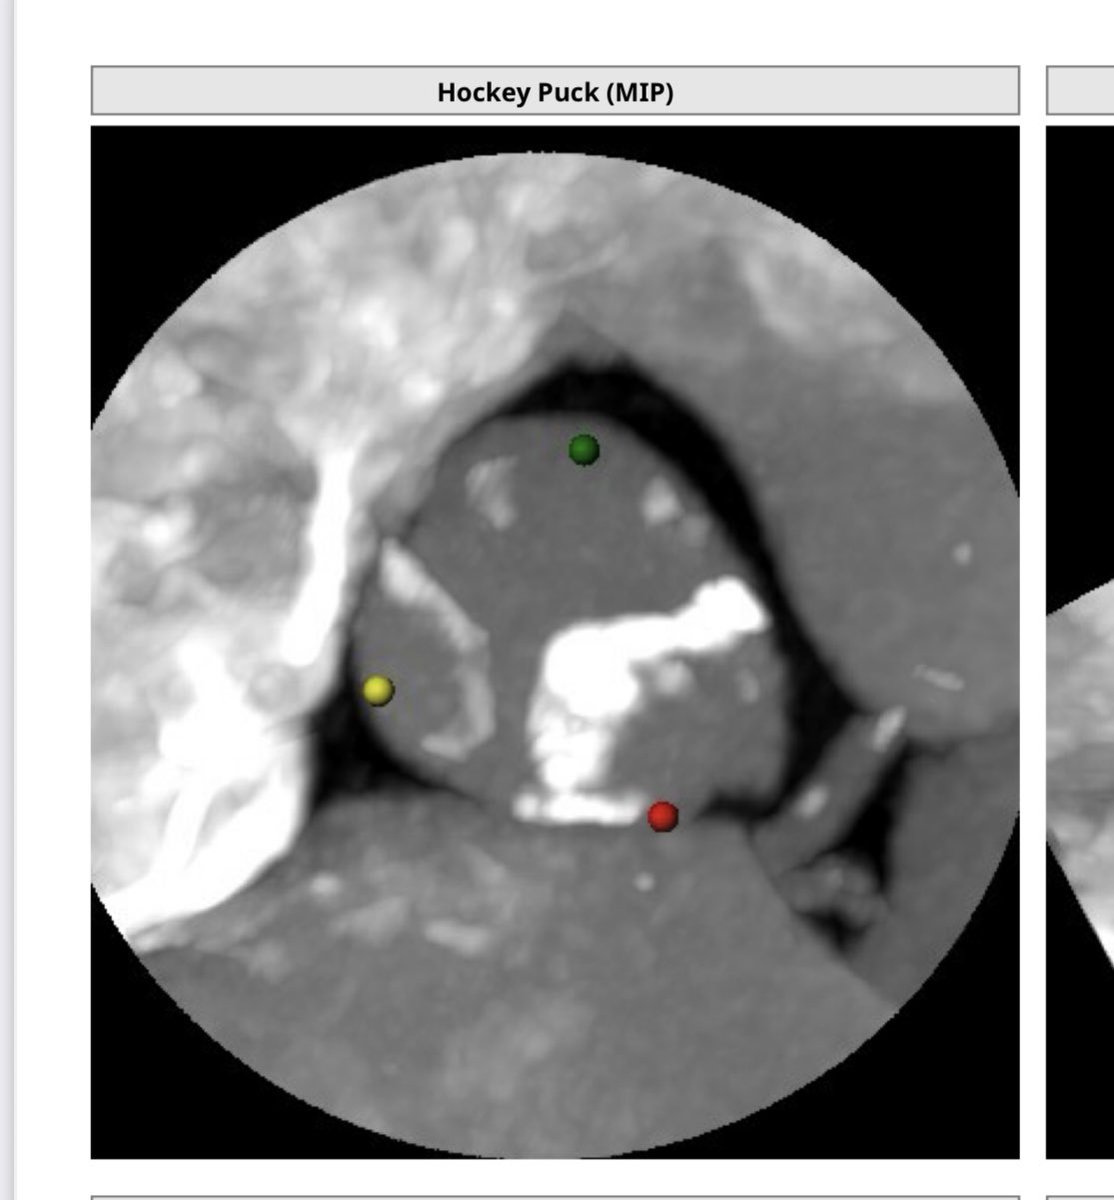

Spooky 3D rheumatic mitral valve eyes👀with commissural fusion! Happy #EchoFirst Halloween! 🎃💀 #CardioX #Cardiotwitter @ASE360 #3DTEE #iecho